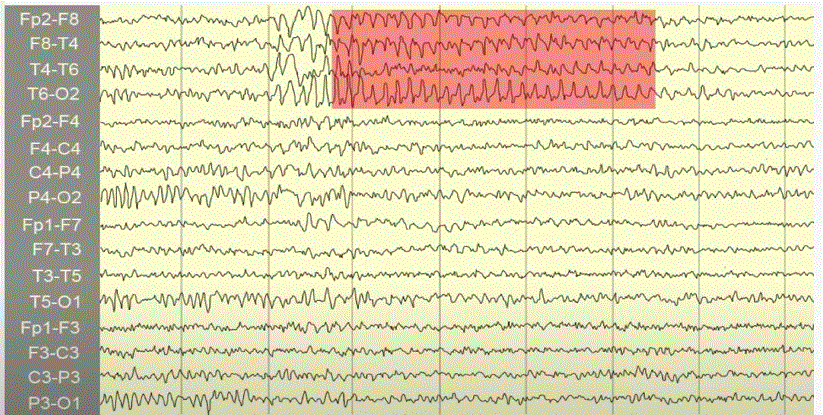

Wicket Spikes

• 6-11 Hz

• Temporal

• Unilateral/bilateral

• Medium-high amplitude

• Older adults

• Drowsy/light sleep

• Arciform/wicket-like appearance